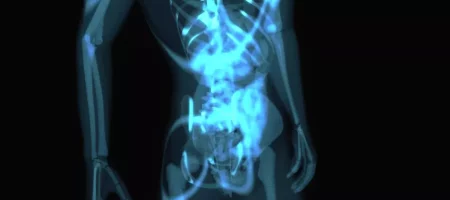

Tüm Vücut MR Nedir? Tüm vücut MR, manyetik rezonans görüntüleme yöntemi ile vücudun baştan ayağa kadar ayrıntılı bir şekilde incelenmesidir. Bu yöntem sayesinde beyin, omurga, boyun, göğüs, karın, pelvis, kas ve iskelet sistemi organları tek bir tetkik ile görüntülenebilir. Amaç, hastalıkların erken dönemde tespit edilmesi ve tedavi planının doğru şekilde yapılabilmesidir. Kanser taramaları, metastaz araştırmaları, […]